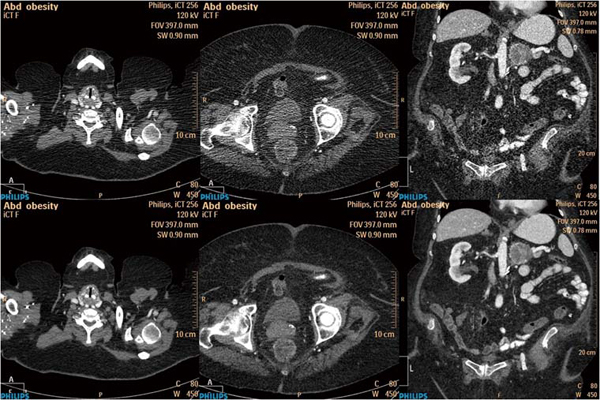

図5は,体重100kgでありながら190mAsで撮影された症例だが,iDoseでは,FBPに比べ肩や骨盤からのストリークアーチファクトがよく改善されているのがわかる。薄いスライス厚のMPRでは,ノイズの低減も顕著に確認できる。

図5 同一データでの比較

上段:FBP 下段:iDose